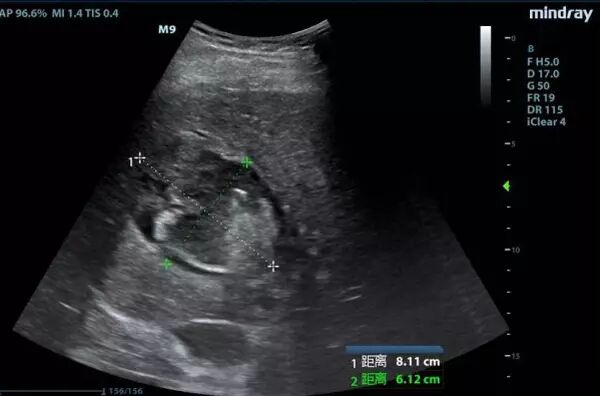

经过抢救团队对症治疗,龚先生的血压慢慢回升,尿量也多起来,乳酸指标有所下降。“在心脏状况这么差的情况下,那怕多一点液体,都有可能成为压死骆驼的最后一根稻草,患者的心脏会承受不了。”值班医生王俊峰运用重症超声这一新型武器,在心脏超声监测下给予精确输液,同时采取其它抗休克措施。经过10个小时的治疗,龚先生乳酸水平终于恢复正常,而且在十多个小时内没有再出现室颤,病情恢复出现良好兆头。

重症超声技术

传统方式下,危重病人是否发生气胸、胸水、肺水肿等,需将病人搬运至放射科做CT等影像学检查,即使床旁X线检查,也要经历拍片、洗片、读片、签发报告等环节。而重症超声因其直观、快捷、准确等特点,可直观报告病情和病因,减少了数据分析的时间,增加了临床判断的准确性,拉近了医生与病因及病情判断的距离,因而被形象地比喻为“看得见的听诊器”。

同时,由于危重病患者多半存在血流动力学不稳定,且可能进行持续机械通气或血液净化治疗,不适宜搬动,这给危重病患者的进一步明确诊断和治疗带来诸多不便。床边超声检查作为一种无创、可重复的检查技术,尤其对于心脏功能、 液体反应性等血流动力学评估作用越来越重要,为重症病人的治疗调整提供及时、准确的指导。